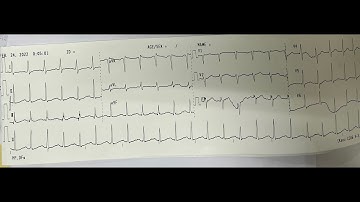

Điện tâm đồ và rối loạn nhịp (ngày 3): ĐTĐ thiếu máu cơ tim